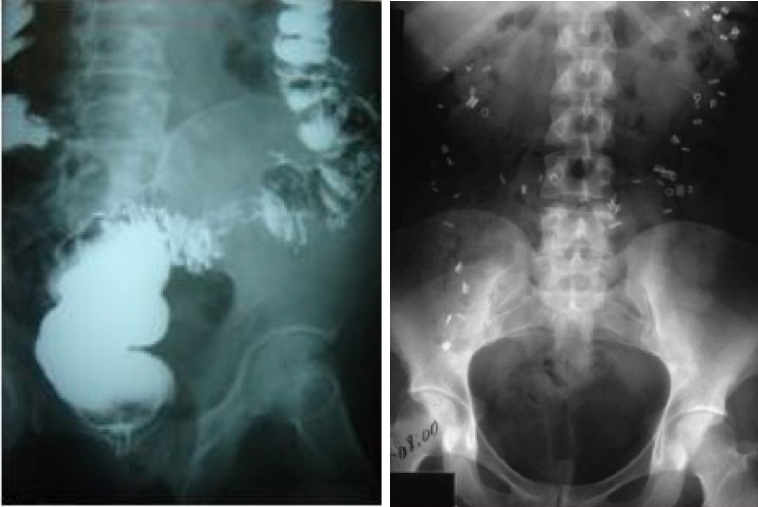

Si. De acuerdo al interrogatorio se eligen los estudios pertinentes. Estos estudios pueden ser desde exámenes generales de sangre y materia fecal, hasta estudios especiales como determinación de hormonas, radiografías (colon por enema, tránsito intestinal y colónico), endoscopía (anoscopía, rectosigmoidoscopía, colonoscopía), Videodefecografía, manometría anorrectal, electromiografía anorrectal, etc. Su médico le indicará cuales debe realizarse. Si desea saber en qué consisten ésos estudios, consulte la sección de “Estudios Especiales” dentro del Menú de “Información para Pacientes.”